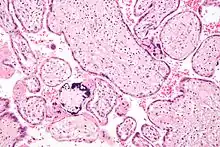

| Micrograph of cytomegalovirus (CMV) infection of the placenta (CMV placentitis), a vertically transmitted infection: The characteristic large nucleus of a CMV-infected cell is seen off-centre at the bottom right of the image, H&E stain. | |